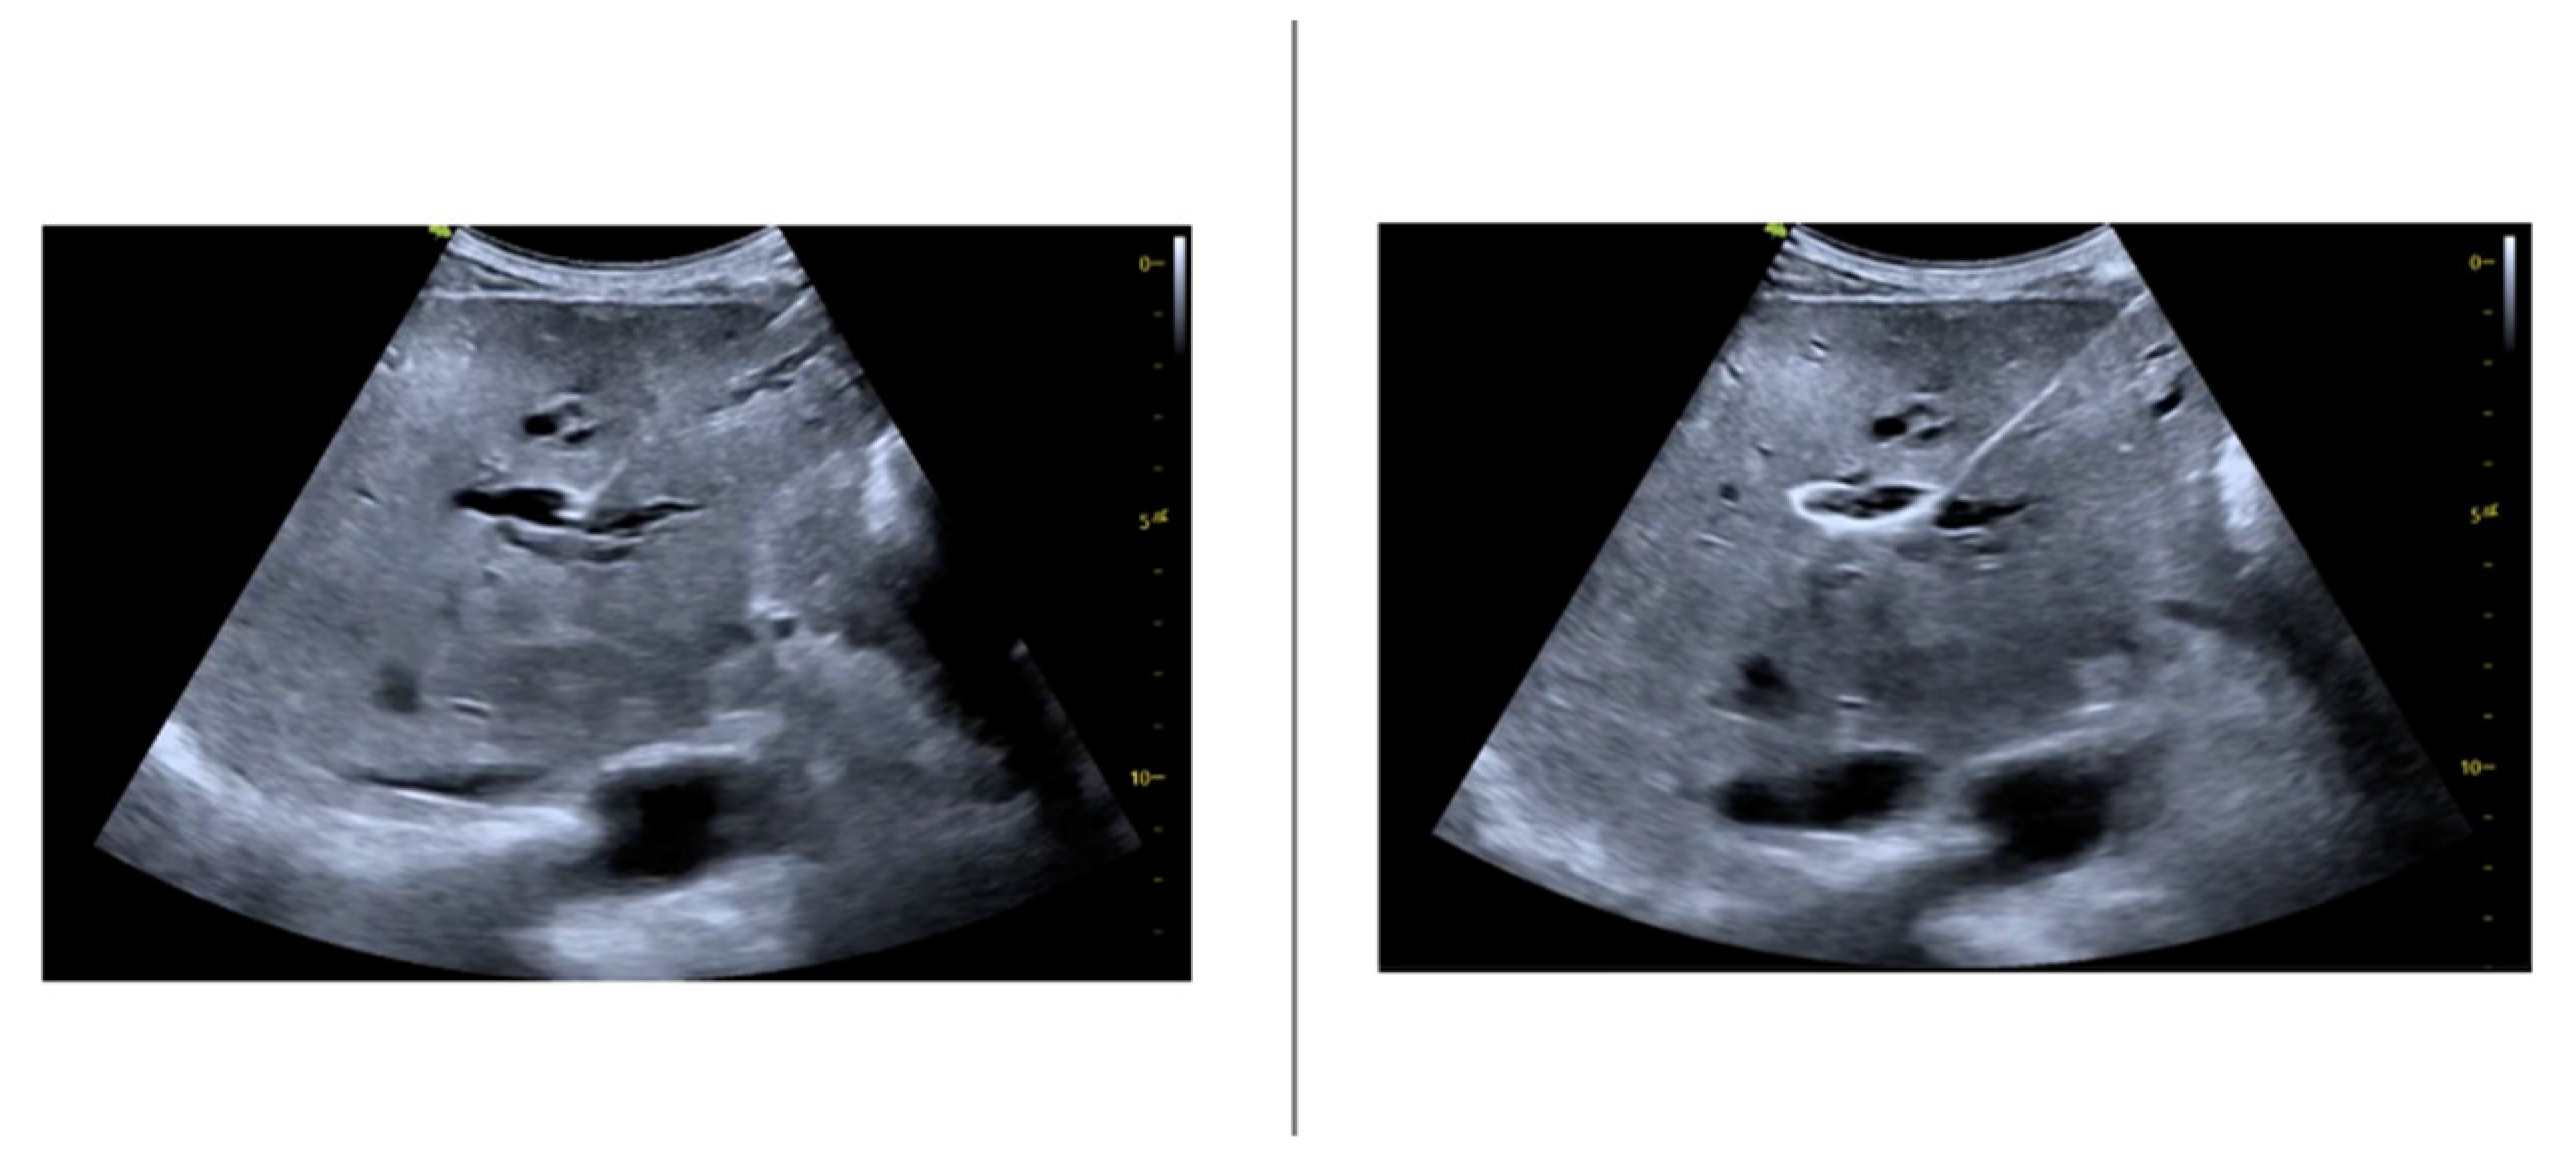

Before every intervention, the patient was induced into deep sedation by an anesthesiologist and, subsequently, a peripheral bile duct was punctured using the fluoroscopy or the ultrasound as guidance. The US-guided puncture was performed with a sterile 22G Chiba needle mounted laterally to the ultrasound probe within a needle guidance system, as shown in the figure (Figure 1).

The ultrasound guidance has made possible the direct visualization of the ductal dilation degree (Figure 2).

Figure 2. Ultrasound images assessing the puncture of the bile duct and the guidewire insertion.